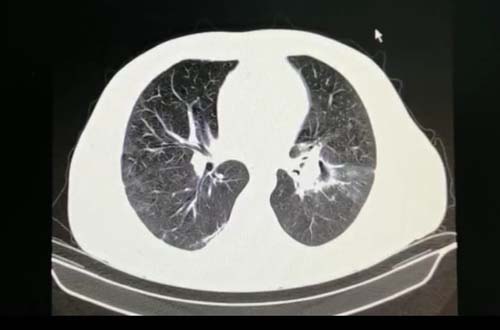

Além disso, a mucormicose tem predileção pelas vias aéreas e pelos pulmões, regiões que já estão comprometidas no paciente de coronavírus. "Isso piora se o paciente estiver com ventilação mecânica, que retira da pessoas todos os reflexos dos pulmões de se autolimparem, como tossir", afirma Otsuka.